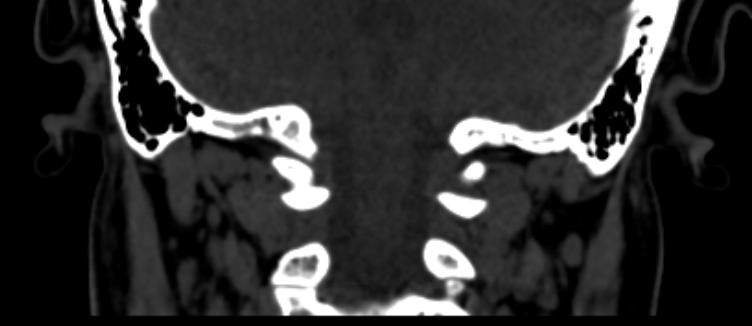

Одним из наиболее информативных методов диагностики заболеваний краниовертебрального перехода является мультиспиральная компьютерная томография с возможностью объемной реконструкции изображений. В основе методики лежит использование рентгеновского излучения. КТ позволяет детально визуализировать костные структуры позвонков, выявить нестабильность суставов, смещение зубовидного отростка и оценить степень сдавления спинного мозга.

В медицинских центрах «Доступная медицина» используются современные 64-срезовый и 128-срезовый компьютерные томографы TOSHIBA AQUILION, на которых проводится сканирование соединения черепа и шейного отдела позвоночника. За счет увеличенного количества детекторов аппараты производят снимки с большой скоростью, которая позволяет минимизировать дозу облучения для пациента. При этом инновационные цифровые приложения позволяют получить объемные изображения исследуемой области высокой четкости, контрастности и в мельчайших подробностях.

При проведении мультиспиральной КТ можно диагностировать различные заболевания, в том числе, аномалии развития краниовертебральной области (как врожденного, так и приобретенного происхождения):

- платибазия (уплощение основания черепа);

- базилярная импрессия (выпячивание зубовидного отростка аксиса в большое затылочное отверстие); ассимиляция атланта (сращение первого шейного позвонка с затылочной костью); атланто-аксиальная дислокация (смещение первого и второго шейных позвонков по отношению друг к другу);

- синдром Клиппеля-Фейля (уменьшение числа и/или сращение шейных позвонков) и другие пороки развития.